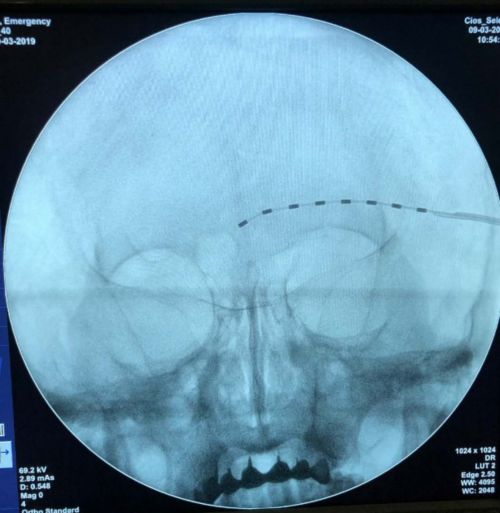

c臂引导下,眶上神经、外周神经电刺激电极植入术。

电极植入部位影像确认。